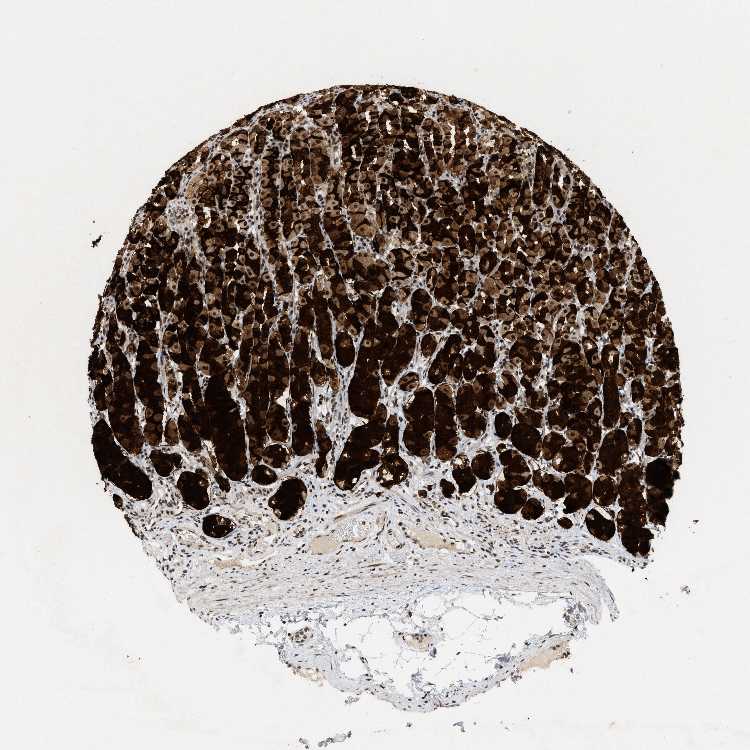

STOMACH 2 - Antibody stainingi

Antibody staining in the annotated cell types in the current human tissue is reported as not detected, low, medium, or high, based on conventional immunohistochemistry profiling in selected tissues. This score is based on the combination of the staining intensity and fraction of stained cells.

Each image is clickable and will lead to virtual microscopy that enables deeper exploration of all samples and also displays staining intensity scores, fraction scores and subcellular localization as well as patient and tissue information for each sample.

Antibody HPA018248Antibody HPA019127Antibody CAB009196

Glandular cells HighHighMedium